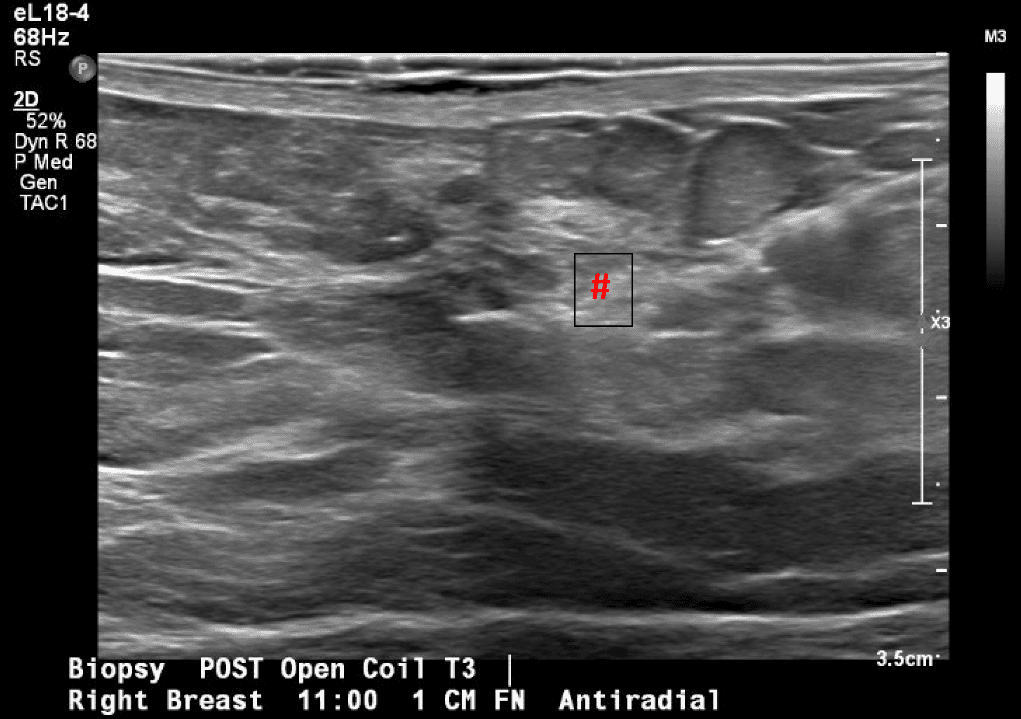

Patient is a 46-year-old premenopausal female with no other contributing past medical or surgical history who presented initially to the breast surgery clinic after her annual screening mammogram discovered a nonpalpable right breast mass measuring 0.6 x 0.8 x 0.7 cm at 11 o’clock (oc), 1 cm from the nipple (FTN) (Figure 1). She had three previous screening mammograms without any notable findings. The screening mammogram was declared inconclusive (BI-RADS 0), and a breast ultrasound was completed with similar findings. Further discussion with the patient revealed that there had been some bloody discharge seen in the right side of her bra over the last few months, but no other concerns or symptoms. Given the inconclusive imaging findings, it was decided to perform a diagnostic mammogram for a more specific assessment (Figures 2a and 2b) following an ultrasound-guided core-needle biopsy and localizing clip placement for a tissue diagnosis (Figure 3). Pathology revealed an intraductal papilloma with ductal hyperplasia and apocrine metaplasia without atypia. Given her continued bloody nipple discharge, there was concern for possible underlying premalignant cells (discussed more later); thus, it was recommended that the patient undergo partial mastectomy. The mass remained nonpalpable; therefore, a Savi Scout would be placed just before operative intervention to help localize the area of concern.

Figure 3. Ultrasound-guided localization and biopsy of the breast mass in question, first seen on screening mammogram. Post-biopsy image includes typical tissue changes seen once a core-needle biopsy is performed (hash mark).